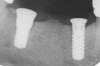

Figure 9  Extraction of teeth Nos. 29 and 31 with immediate implants (Straumann USA, Waltham, MA) placed into the site.

Figure 9

Figure 10  Implants seen in Figure 9 restored approximately 3 months after placement.

Figure 10